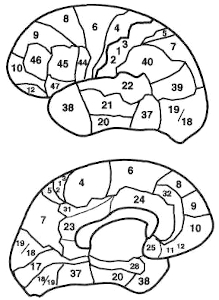

La figura 2-5 es un mapa de uso frecuente, basado en las áreas citoarquitectónicas (regiones de arquitectura celular distintiva) de la corteza cerebral. Se conoce como Mapa de Brodmann y las zonas están designadas con números.

Figura 2-5. Mapa de las principales áreas que identificó Brodmann en sus estudios de arquitectura celular (citoarquitectura). No es una cartografía frenológica ni un mapa moderno de las funciones del cerebro, sino sólo una referencia anatómica conveniente. Algunas áreas son demasiado pequeñas y no se las puede describir aquí, o se esconden en las grietas. La imagen superior muestra la zona externa del hemisferio izquierdo; la inferior, el aspecto interno.